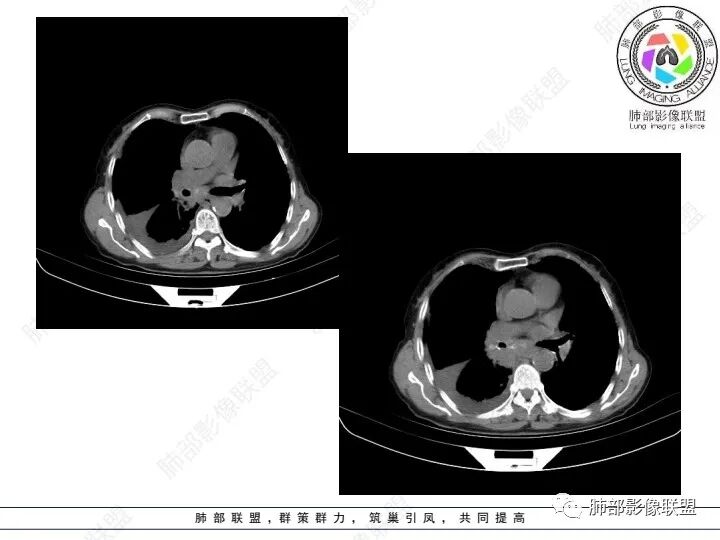

双肺间质性改变,右肺下叶支气管环形增厚,支气管变窄,周围见钙化影,右肺下叶软组织占位,明显的坏死,明显环形强化,两侧肺门及气管隆突下淋巴结肿大。右侧胸腔积液,肝脏周围少量腹腔积液,老年女性患者腹痛便血,Ca125明显增高。考虑1一元论:腹腔恶性肿瘤(胃肠道或卵巢来源)肺内及胸膜腹膜转移;2二元论:右下肺粘液表皮样癌/腺样囊性癌,腹腔胃肠道或卵巢来源肿瘤。

良孑:

3、胸部增强CT示右肺下叶脊柱旁不规则软组织肿块,侵及壁层胸膜外,密度不均匀,不均匀强化,中心低密区可疑坏死,右侧胸腔积液、胸膜结节影或结节样增厚,增强扫描可见强化,右侧肺门及纵隔内可见淋巴结肿大、融合,右侧中尖段支气管及右肺下叶支气管受侵,管腔狭窄。

4、综上,老年男性,CA125升高,右肺下叶肿块侵犯胸壁,伴纵隔、右肺门及纵隔淋巴结肿大,右侧胸腔积液、胸膜增厚伴结节影,强化明显,应该为一较典型的肺癌伴肺胸膜腔及肺门纵隔淋巴结转移,尤其是肺腺癌。